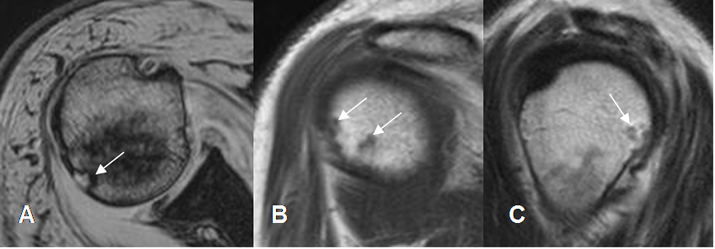

Fig 96. Pinzamiento posterosuperior.

A: RM axial en FFE, B: RM sagital en T1 y C: RM sagital en T2. Lesiones osteocondrales en la parte posterosuperior de la cabeza humeral, por pinzamiento.